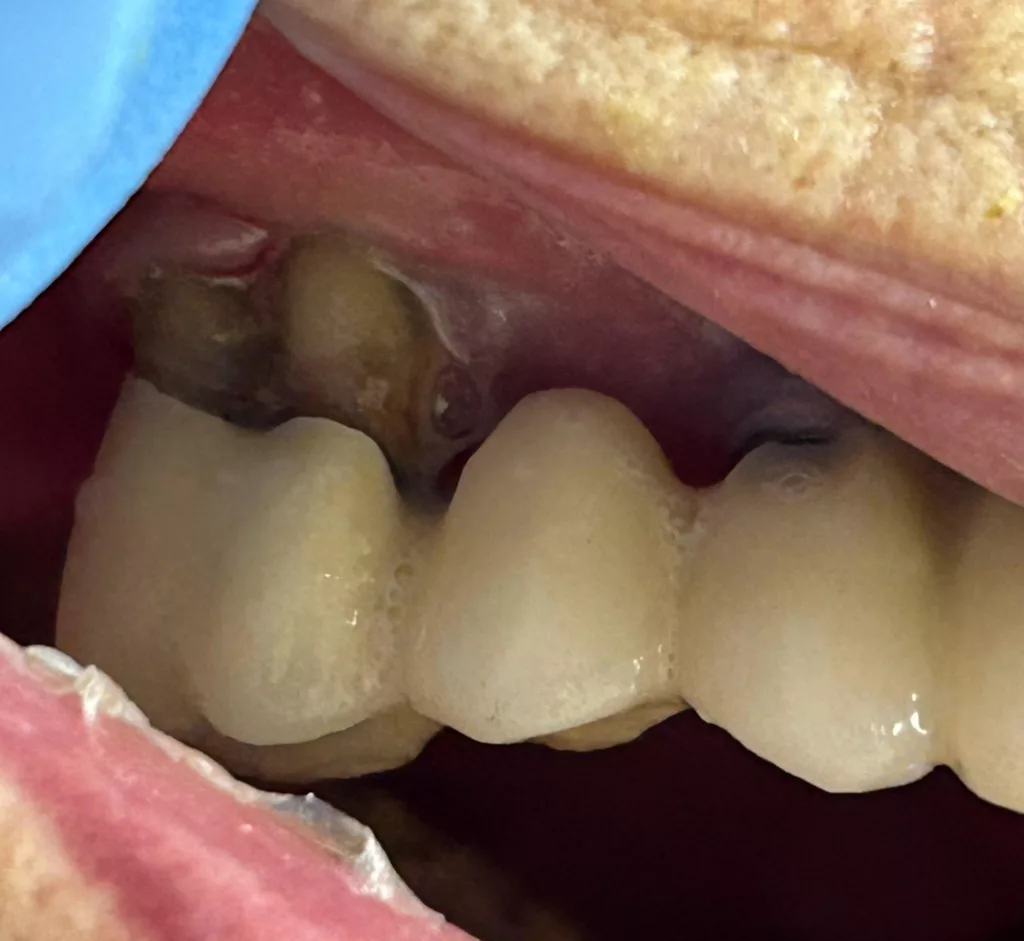

Von einer Polymedikation sind besonders multimorbide Pflegebedürftige betroffen. Hier kann die Kombination von Krankheit und Arzneimittel erhebliche Auswirkungen auf die Mundgesundheit haben. Die Xerostomie ist eine davon. Mundtrockenheit entsteht häufig durch die Einnahme von Antihypertensiva, Antidepressiva, Diuretika oder Parkinsonpräparate [9,10]. Doch der Speichel hat als natürlicher Schutzfaktor eine wichtige Funktion: Dazu zählen Neutralisation von Säuren, Remineralisation des Zahnschmelzes, Reinigung der Mundhöhle und Schutz vor Infektionen [11,12]. Fehlt der Speichel, entsteht ein trockenes, oft brennendes Mundgefühl, Pflegebedürftige können sich nicht mehr mitteilen – die Zunge klebt am Gaumen. Es kommt zur schnelleren Plaquebildung, was das Risiko für Karies, Gingivitis und Parodontitis (Abb. 1 und 2) deutlich erhöht.

Pflegende sollten daher die Symptome von Xerostomie erkennen, um passende Maßnahmen einleiten zu können, z.B. eine gezielte hochkonzentrierte Fluoridanwendung oder die Empfehlung feuchtigkeitsspendender Präparate [13,14]. Besonders kritisch ist die Situation, wenn ein vorhandener Zahnersatz aufgrund seiner Komplexität schwieriger zu reinigen ist (Abb. 3–5).

Ein 88-jähriger Patient, Pflegegrad 4, nach Apoplex pflegebedürftig, lebte in einem Pflegeheim, wo er täglich von seiner Frau besucht wurde. Er litt an einer rechtsseitigen Parese, war sprachlich und feinmotorisch stark eingeschränkt. Seine Polymedikation war dem allgemeinen Gesundheitszustand und dem Diabetes angepasst. Der Ober- und Unterkiefer des Patienten war mit festsitzendem Zahnersatz, bestehend aus Kronen, Brücken und zwei Inlays, hochwertig versorgt. Die Mundhygiene wurde vom Patienten selbstständig durchgeführt, während sich das Pflegepersonal auf vorbereitende Maßnahmen beschränkte – mit mangelhaftem Ergebnis.

Die Präventionsmaßnahmen und die Inspektion in der Praxis offenbarten einen Plaque- und Blutungs-Index von nahezu 100%. Speisereste, subgingivale Konkremente und eine massive Entzündung des Parodontiums. Des Weiteren fehlte dem Patienten die Frontzahnkrone 21. Es galt, weiteren gesundheitlichen Schaden vorzubeugen.